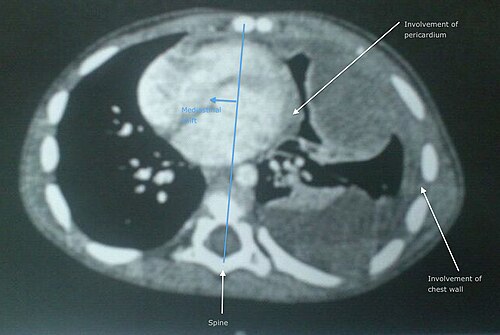

Diagnosis is established by core needle biopsy often performed by interventional radiology teams at centers like Brigham and Women's Hospital with staging using cross-sectional imaging including MRI protocols standardized by radiology societies and PET/CT modalities available at facilities including Memorial Sloan Kettering Cancer Center and Stanford University Medical Center. Staging follows systems promulgated by the American Joint Committee on Cancer and informed by trials from cooperative groups such as the Children's Oncology Group for pediatric cases; staging determines surgical planning similar to approaches developed at MD Anderson Cancer Center.